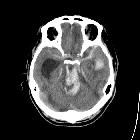

Duret hemorrhage is a small hemorrhage (or multiple hemorrhages) seen in the medulla or pons of patients who are rapidly developing brain herniation, especially central herniation.

Raised supratentorial pressure causes the brainstem and mesial temporal lobes to be forced downwards through the tentorial hiatus. As a result of this shift, it is believed that perforating branches from the basilar artery and/or draining veins are damaged with resultant parenchymal hemorrhage. Most commonly it is seen in patients with severe herniation 12 to 24 hours prior to death .

The classical appearance of a Duret hemorrhage is a single small, round hemorrhage located in the midline of the medulla or pons near the pontomesencephalic junction. Often, however, these hemorrhages can be multiple or even extend into the cerebellar peduncles.